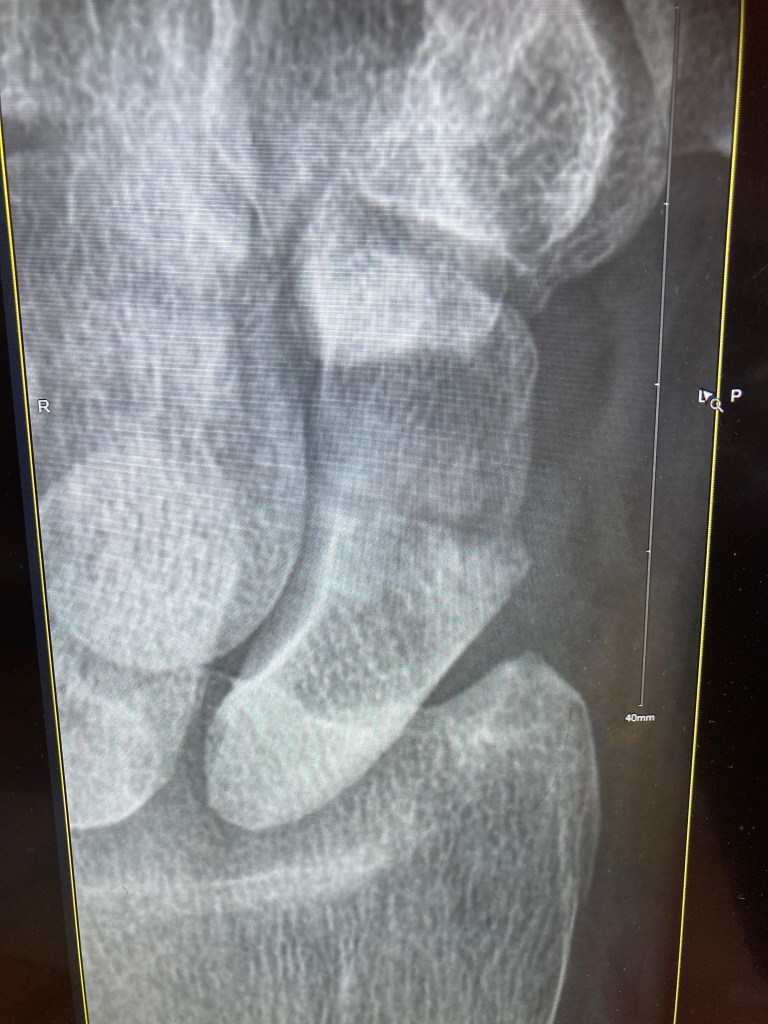

I was back in the hospital today. Arrived early, at about 8am. Still, the outpatients department was bustling with staff, and crocks like me. I had hardly taken my seat when I was asked to head on down to the x-ray department for a scan on my wrist. Oh good… and what about my back? Sorry? Yes, my back; that should be x-rayed as well? Sorry, it’s not listed here…

Ho, hum. I went down anyway, and they dutifully scanned the wrist in its cast. I asked him about the back. No dice, without that little slip of paper. He did try to ring back up to the OPD, but there were no doctors in until nine. I returned back to my seat, and met Dave, the young doctor who had looked after me in the ED and had seen me a few weeks ago. I mentioned the lack of spine scans, and he shook his head and sighed, and within minutes, I was heading back down to the x-ray department for a second set of scans.

Back up to the OPD. Retake my seat. Wait. Get called by nurse. Please head up to the cast room. Odd. Same wonderful lady who put on my previous cast, who proceeds to whip out a menacing circular saw to remove the cast, sawing two neat lines, top and bottom, and, using a nifty pair of stainless steel spreaders, cracking the whole thing open with the gusto of someone about to tuck into a lobster. (Ed. Are you sure about this metaphor?)

Dave reappears to explain that the wrist scans were a little grainy, so they send me back down to the x-ray department for a third time. I should be getting frequent flyer miles. Though I suppose I mustn’t grumble… (it’s all part of the health service we pay for in taxes), and indeed, I don’t grumble, despite Dave apologising several times, I laugh it off, and point out that I’m really not doing anything else at the moment, and I have four hours in the meter outside. We’re all good.

The upshot of all this scanning is that things are going in the right direction. The cast will hopefully come off in two weeks, which is sooner than I thought. But I won’t object. The back brace can be relaxed around the house, and just worn if I am heading out or doing any activities like dog walking. And in about four to six weeks, we can start doing some actual exercises, such as yoga (Dave’s suggestion), and swimming. In the meantime, I will do some work on the spin bike upstairs, starting tomorrow.